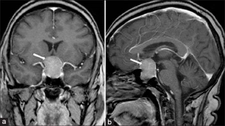

Hipofiz Bezi Tümörlerinin TeşhisiHipofiz bezi tümörlerinin teşhisi genellikle aşağıdaki yöntemlerle yapılır: